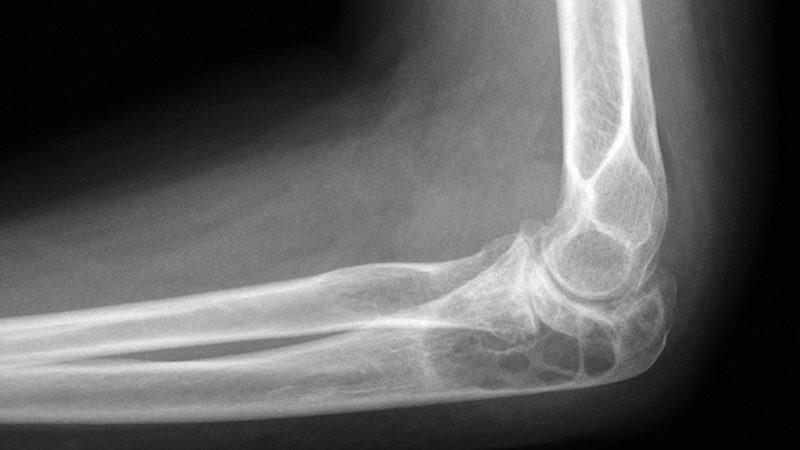

Фото артрита локтя: